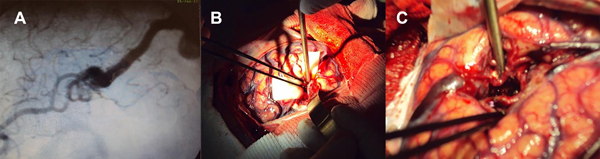

Figura 2: A: MAV grado I en angiografía; B- micro disección e identificación de los pedículos de la MAV, obsérvese la arterialización del drenaje venoso único.; C: Micro disección del surco, con resección del ovillo y el shunt AV interrumpido con la restauración del flujo venoso normal y preservación de los vasos pasantes.